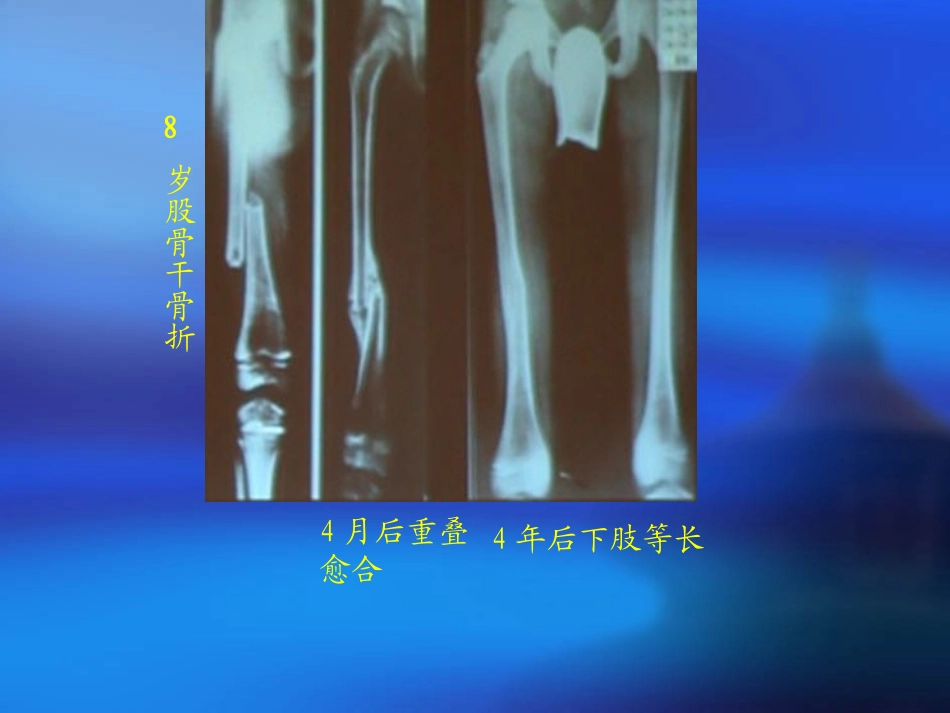

儿童股骨干骨折河南大学淮河医院“小儿不是成人的缩影”儿童骨折具有独自的特点甚至某些治疗原则与成人截然不同!4年后下肢等长4月后重叠愈合岁股骨干骨折8概述儿童股骨干是一种较为常见的骨折,好发于婴幼儿,占小儿下肢骨折的10.6%。骨折多为强大暴力所致,治疗后通常有轻度的旋转畸形,但会随生长而矫正。儿童股骨骨折的治疗逐步朝向手术治疗的方向发展。肥厚的骨膜骨骼有巨大的可塑性能在发育过程中矫形能力强骨折愈合快关节僵直少见:固定时间<3周儿童股骨干骨折特点1.能早期形成丰富的骨痂达到坚固愈合;2.有明显的过度生长,具有一定的自然矫正畸形的能力;3.愈合快,预后好,通常保守治疗可治愈。影像学要点•包括上下两关节,以免漏诊;•近端:髋脱位、股骨颈骨折或转子间骨折;•远端:膝关节的骨骺损伤、韧带损伤、半月板撕裂及胫骨骨折;•骨扫描及MRI非必需,应力骨折及有跛行表现的嵌插型或青枝骨折。骨折分类骨折位置分类:上段(粗隆下)、中段、下段。形状:横行、螺旋、斜行、粉碎与非粉碎性。开放与闭合骨折,是否合并血管神经损伤儿童骨折50%以上是单一横断、闭合、非粉碎性的诊断骨折“三主征”:畸形、异常活动、故擦音骨擦感。一般体征:疼痛,肿胀,功能障碍。多发伤或合并颅脑损伤以及不能行走的诊断困难单纯股骨干骨折很少引起低血压,Hct很少低于30%,否则要排除其他失血原因;治疗治疗原则:1.治疗目标是使骨折短缩小于1cm,无成角,无旋转畸形。2.精确的解剖复位对取得优异的效果来说是不必要的。3.对位力线好比骨断端良好更为重要。4.小儿年龄越小,恢复正常骨结构可能越大,对位对线要求越低。5.治疗方法个性化:年龄、皮肤情况、骨折平面、移位情况,是否复合伤。治疗:皮肤牵引1.传统治疗多采用双下肢垂直悬吊皮肤牵引,但由于垂直悬吊皮肤牵引常不能使骨折解剖复位,易造成肢体早期不等长、畸形等并发症,小儿皮肤易对胶布过敏起水疱而引起哭闹,该方法已渐不能为广大患儿家长所接受。适用于3岁以下或体重不超过7kg的婴幼儿,用胶布两根贴于患儿双下肢内外侧,长度达于大腿根部,或牵引自骨折水平面或以上lcm处开始,双下肢同时牵引,两腿垂直向上悬吊,重量以患儿臀部稍稍离床为度,健侧稍轻于患侧,为防止发生向外侧成角畸形,加用夹板固定,患儿面向健侧躺卧,定期摄片,了解骨折复位情况。治疗:悬吊牵引治疗:支具或石膏裤固定国外常用而首选方法。Pavlik或者屈髋30°外展30°屈膝30°髋人字石膏(该年龄段骨折塑形潜力大,无论初始短缩和对线如何,其结局一般较好)。治疗:弹性髓内钉(6-14岁)其他治疗:水平皮肤牵引,骨牵引,小夹板外固定+牵引,钢板,经皮穿针等等。任何年龄段可供选择的治疗方法:外固定支架固定。外固定支架固定治疗小儿股骨干骨折利于弊提供快速、坚强固定切口小失血少损伤小骺板损伤和AVN风险低避免二次手术钉道刺激、感染难看的钉道瘢痕令人悲催的再骨折利弊儿童骨折保守治疗可获得满意的结果,骨折不愈合、延迟愈合极为罕见手术治疗儿童骨折渐多,但问题也逐渐增多!!!儿童骨折治疗原则治疗本身不能影响骨的生长尽可能手法整复,保守治疗,勿轻率切开复位整复时争取解剖复位,但接受功能位置整复时不要造成新的损伤高能量创伤,开放性损伤的增加家长对骨折复位的要求越来越高手术治疗儿童骨折呈增多趋势复位要求轴线——恢复正常成角——注意矫正旋转——必须矫正关节内骨折——解剖复位儿童骨折的手术治疗关节内移位骨折开放骨折合并血管、神经损伤多发骨折钢板、外固定架、髓内针视病情合理使用避免使用环形内固定物,影响血运及骨愈合内、外固定不当髓内钉的选择螺钉经过骨折线,骨折远或近端仅有1枚螺钉固定股骨干石膏固定应使用髋人字石膏,长腿石膏托/管型的杠杆作用不利于骨折愈合术后9个月骨折不愈合、再移位术后6月术后9个月骨折不愈合5岁股骨干粉碎骨折术后16月6岁以下儿童股骨干骨折慎选切开复位,钢板螺钉固定的创伤大幼儿骨骼对螺钉的把持力与成人有区别儿童不是成人简单的成比例缩小具有独特的解剖...